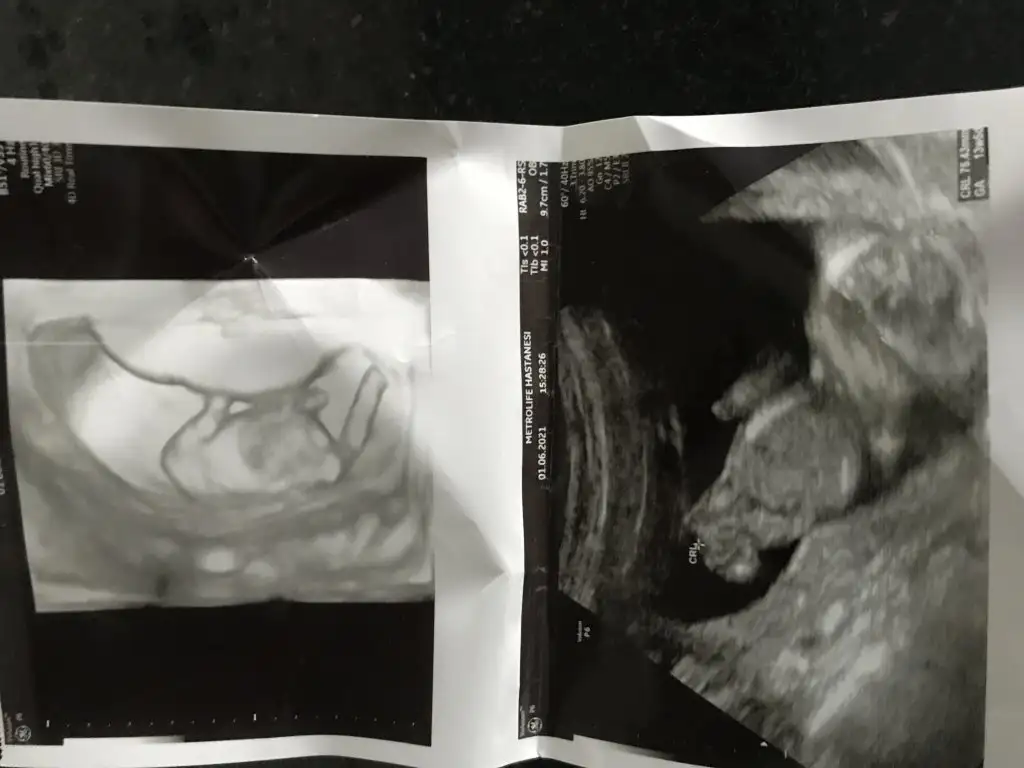

Az önce dr dan geldim. Bana kız dedi ya 17hafta olduk. 12.haftada da kiz demisti. Tum belirtilerim erkekti amaErkek görünüyor![]()

Kız görünüyorYenisi ekledim![]()

Kız gibi sanki daha önceki karanlık USG emin olmamıştımBen bugün gene kontroldeydimIkra meyra her seferin farklı tahminde bulunuyor ama bugün met ve emin söyledi. Bakalım sen ne diyeceksin? Bemce poposu dönük ama öyle bişey demedi.

Evet bu sefer de kız dedi kesin konuştu ama ben 20. Hafta detaylıyı beklecepim emin olmak için. Teşekkür eserimKız gibi sanki daha önceki karanlık USG emin olmamıştım